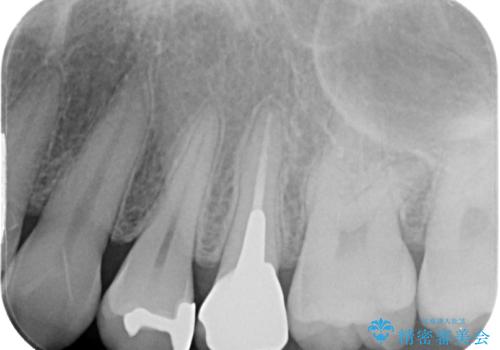

銀歯を気にせず思いっきり笑えるようになったと大変喜んでいただきました。

機能面においても問題なく、適合性の良い被せものをセットすることができました。